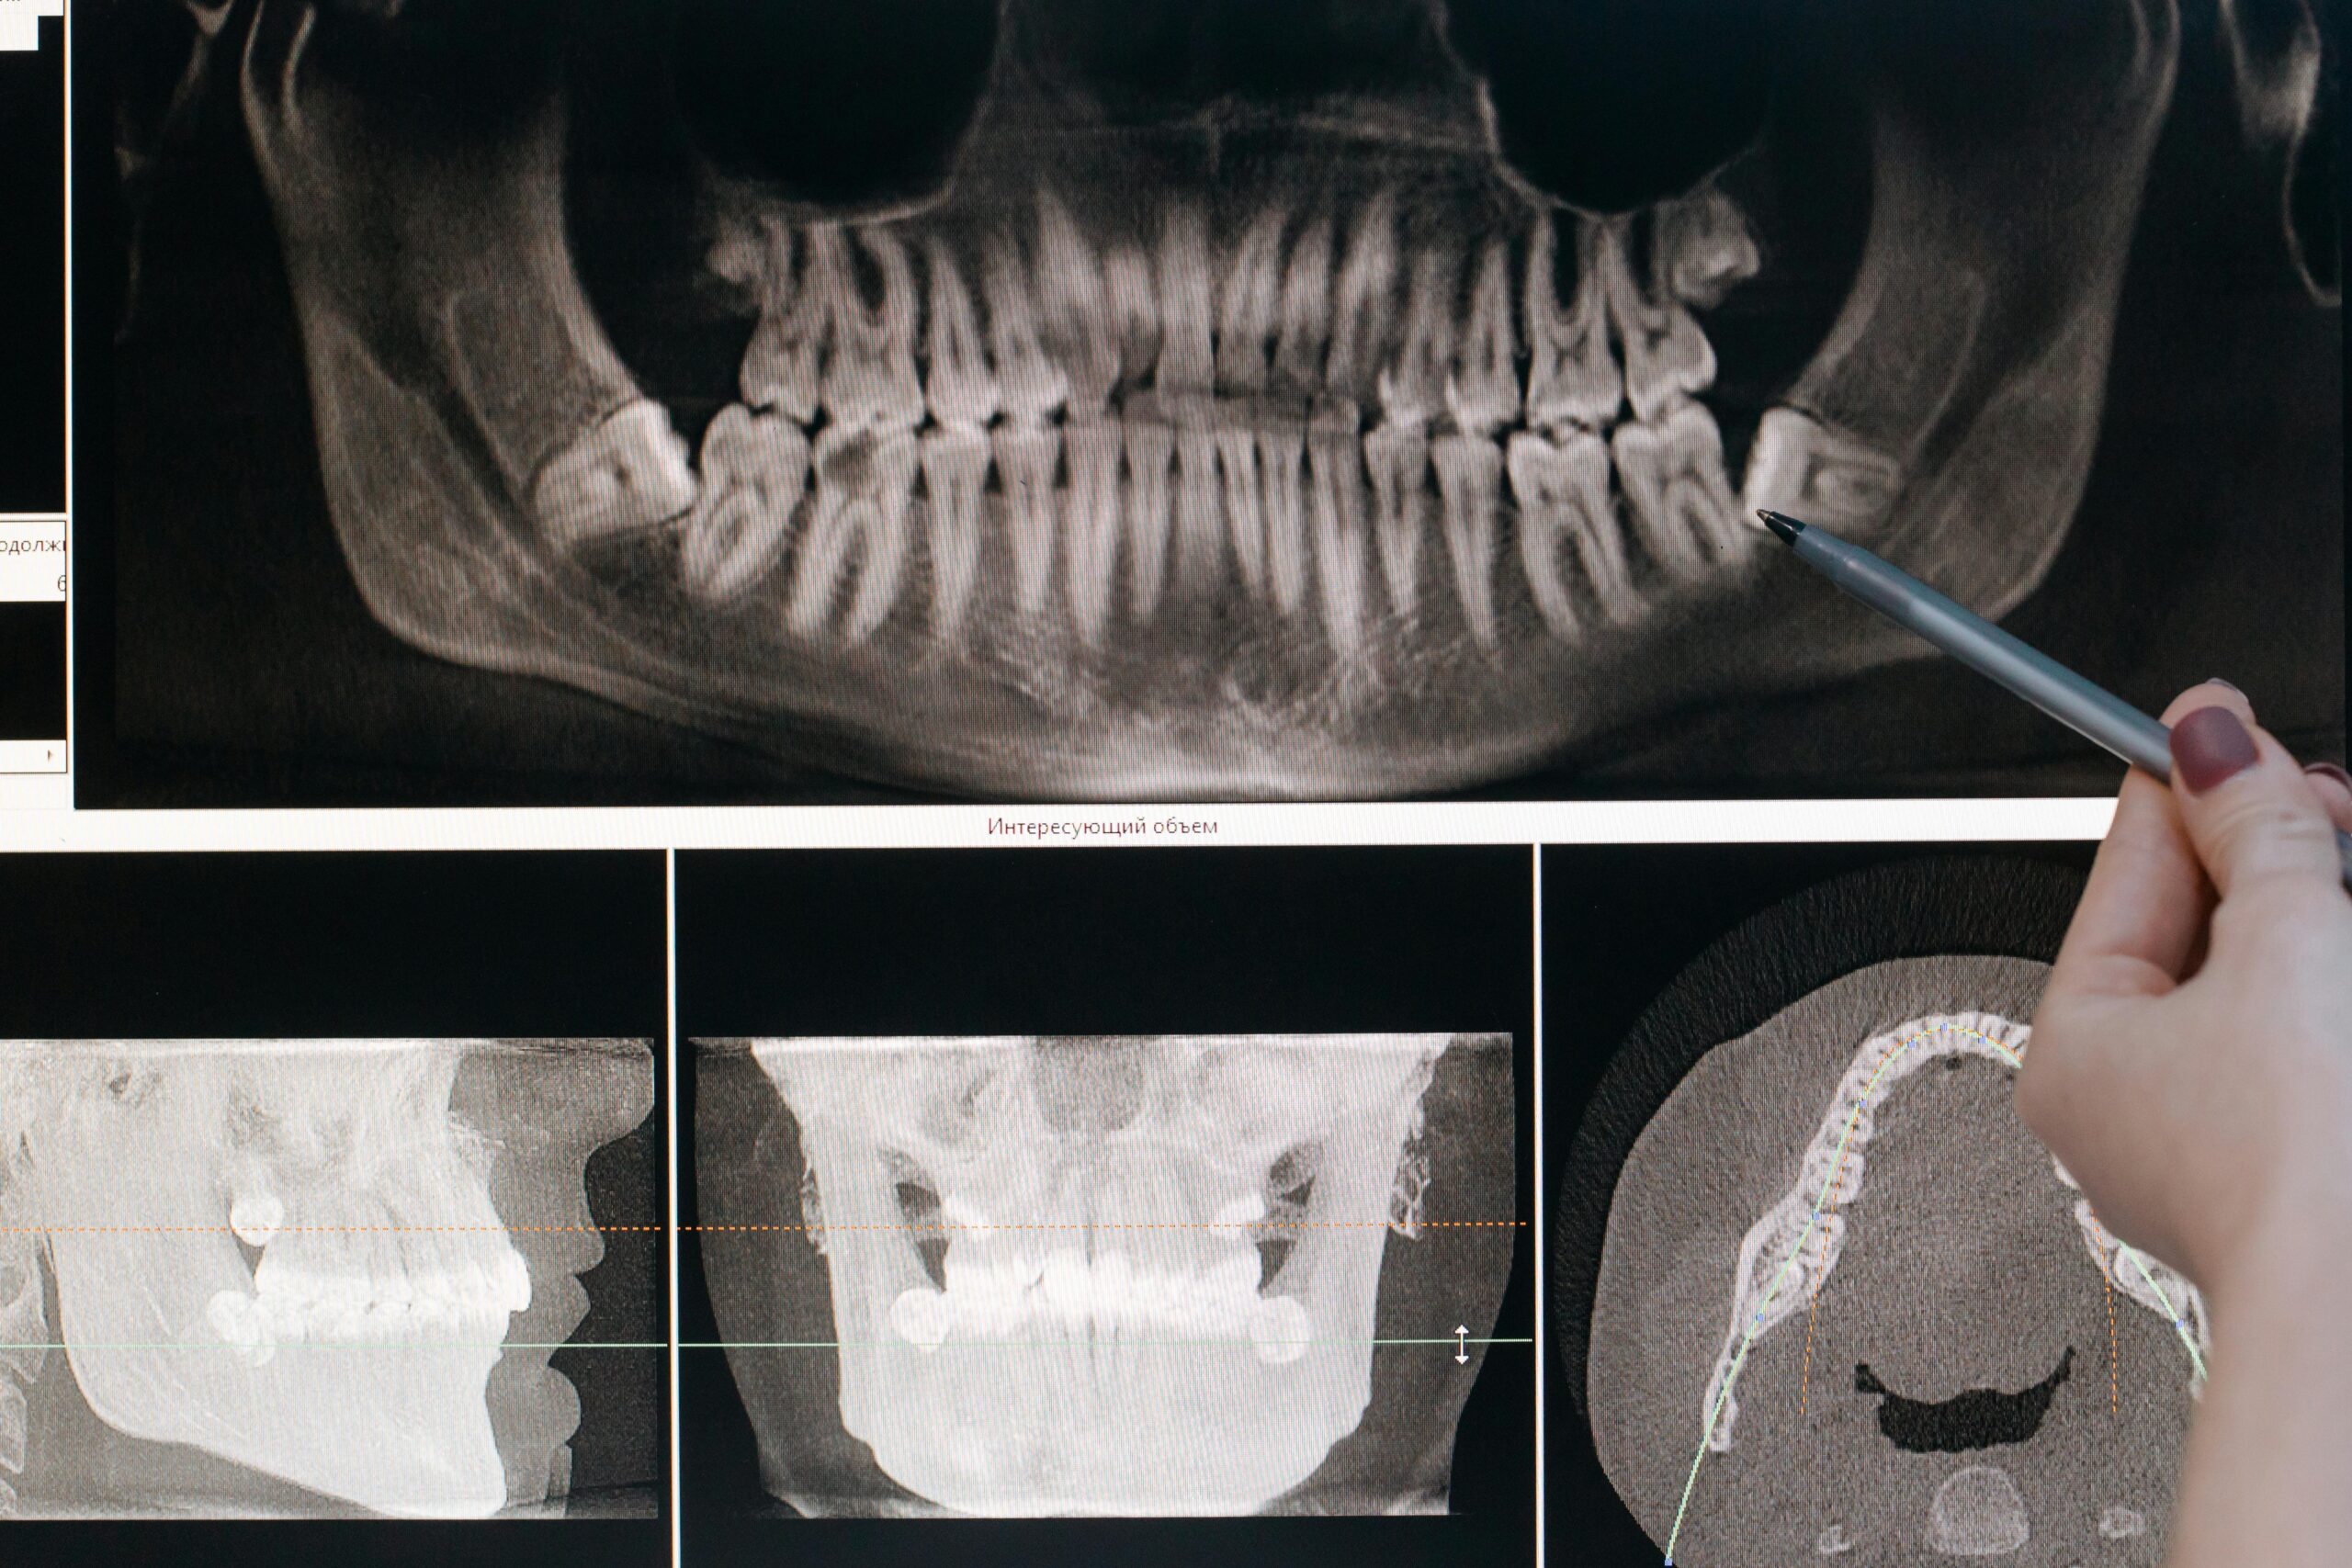

3D Cone Beam CT Scan

Detailed Imaging for Safer Extractions

This scan provides a full 3D view of your wisdom teeth, nerves, and jaw structure, helping your dentist plan the extraction with accuracy and minimise complications.

Your dentist will examine your mouth and take digital x-rays to assess the positioning of your wisdom teeth. If removal is recommended, sedation options may be discussed for your comfort. The procedure is performed with precision to ensure a smooth recovery.

A detailed assessment is done using X-rays or scans. Your dentist explains the type of extraction needed, sedation options, and what to expect during recovery.